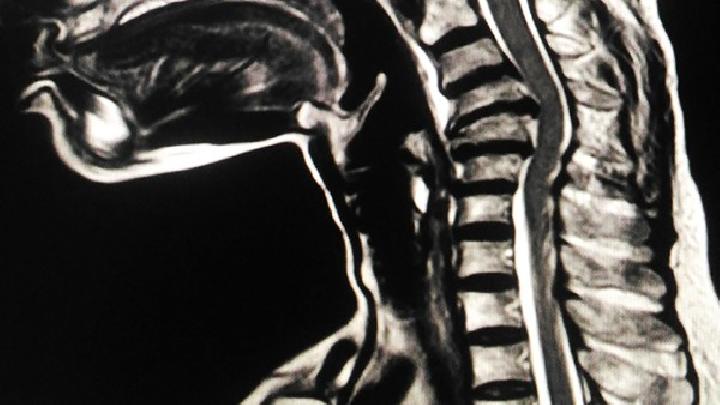

CT检查是诊断极外侧型腰椎间盘突出症的重要方法,能够较为清晰地显示椎间盘突出的位置和程度,在临床上应用广泛,为避免误诊漏诊,CT检查时应全面扫描,排查肿瘤可能性,必要时可进行CT椎间盘造影进行确诊。